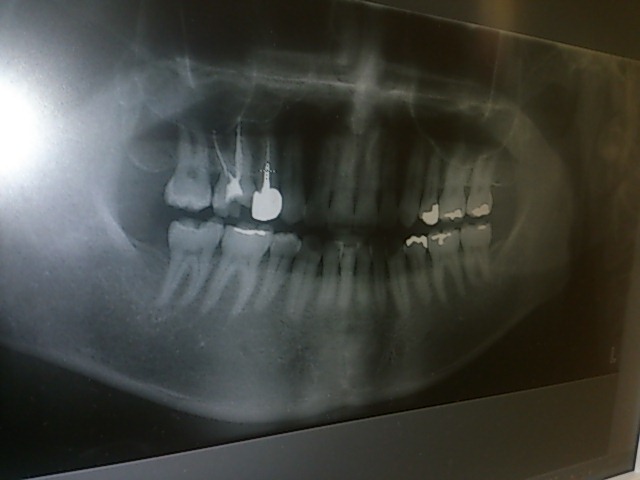

数ヶ月前に歯医者のふざけた診察を書いたのだけど、 その時通っていた歯医者はすでに変えていて 今はほとんどストレス無い歯医者通いをしてるのですよ。 以前の歯医者を治療途中で変えたので、またレントゲンから始まって 治療費がかさんだのだけど今回の歯医者は要領が良いというか、1回の治療で 40分ぐらいやってくれるので治療が早かったのですよ。 そして今回そこの歯医者でセラミックという材質の義歯がある事を聞いて どうしようか迷い中! 昔、よく虫歯を作ったせいかやたら銀色の詰め物があるのですわ。 しかも神経の無い歯があったりして、歯の色が変わってきてるので この際、口を開けて目立つ銀歯をセラミックやらという耐久性のある 義歯に変えようか悩み中なのよ。 先生にちょっと写真撮らせてくれと頼んで撮った自分の歯のレントゲン(笑) 白く写ってる部分が銀歯箇所。 ただそのセラミックという材質は保険が効かないみたいなで、 1本につき5万円~みたい。 ちょっと高いけど後々の事考えたら、何本か綺麗にしたいのが正直なところ。 う~ん、やるか。 音楽の方は今週ヘヴンスリハーサルに入りますわ。 久しぶりに音合わせして色々進めていえればいいですな。 昔載せた写真だけど、自宅音楽部屋はこんな感じ。 ドラックはやってないですよ。 あくまでインテリアのタペストリー(笑) PR